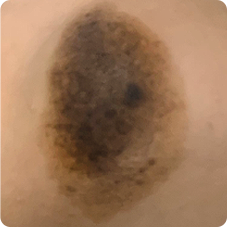

반문상 모반은 밀크모반과 멜라닌 모반이 혼재된 것으로 밀크색 바탕에 까만색 멜라닌 모반이 다양한 형태로 섞여 있는 모습을 보입니다.

일반적인 색소 토닝으로 치료가 되지 않으며, 장기적인 플랜으로 레이저 치료를 진행해야 합니다.

병변 사이즈가 작거나 신속한 제거를 원하는 경우 수술로 빠르고 확실하게 치료할 수 있습니다.